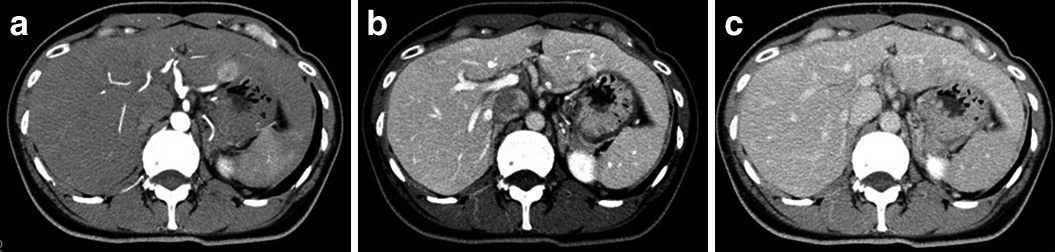

腹部ダイナミックCT所見:術前CT(Fig. 2a:動脈相,b:門脈相,c:平衡相):肝表面は整,辺縁は鋭であり腹水は認めなかった.肝S2に単発で2.0 cm大の占居性病変を認め,early enhance/delayed wash-outを示した.明らかな脈管侵襲は認めなかった.

Enhanced CT demonstrated clearly a demarcated high density tumor (20×18 mm) in the arterial phase (a). Delayed wash out was revealed in the portal and late phase (b, c).

左肝動脈は胃十二指腸動脈から分岐する破格を認めた.